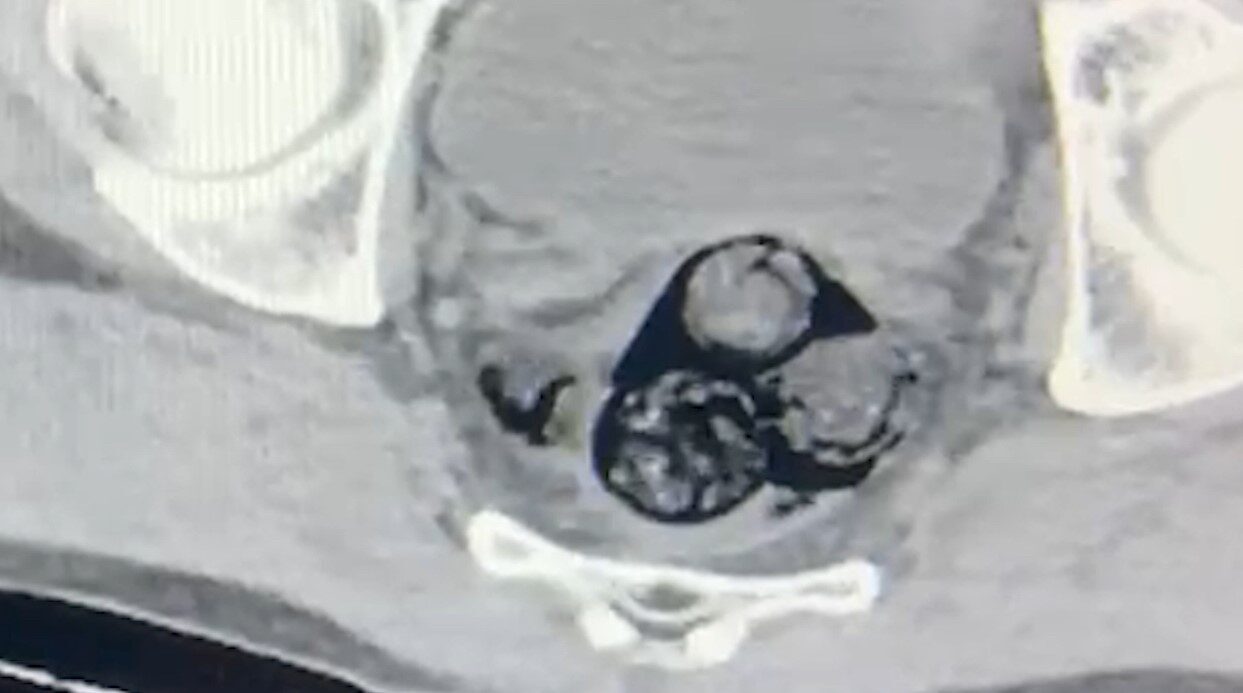

Iğdır İl Emniyet Müdürlüğü Narkotik Suçlarla Mücadele Şube Müdürlüğü’ne bağlı ekipler, A.İ.’yi yakın takibe aldı. Gerçekleştirilen ayrıntılı aramalar, şahsın vücut boşluklarında uyuşturucu madde bulundurulduğunu ortaya çıkardı. Radyolojik inceleme sırasında, A.İ.’nin makat bölgesinde dört ayrı yabancı cisim tespit edildi.